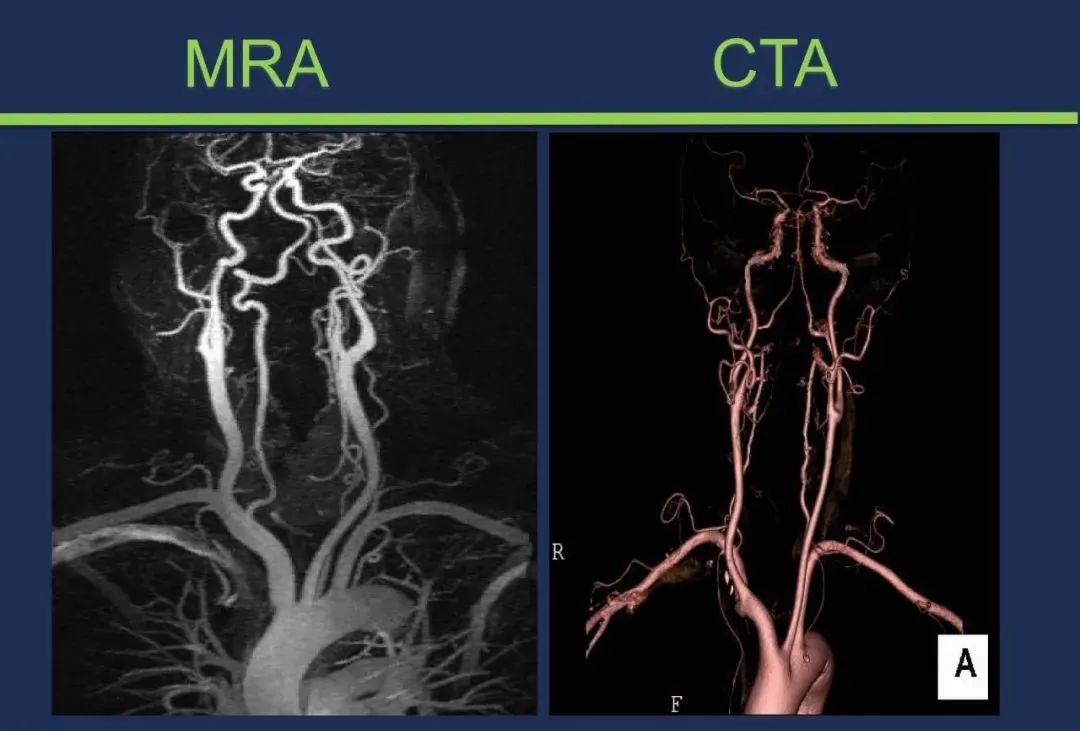

从梗死部位推测责任血管:脑血管解剖

从梗死部位推测责任血管